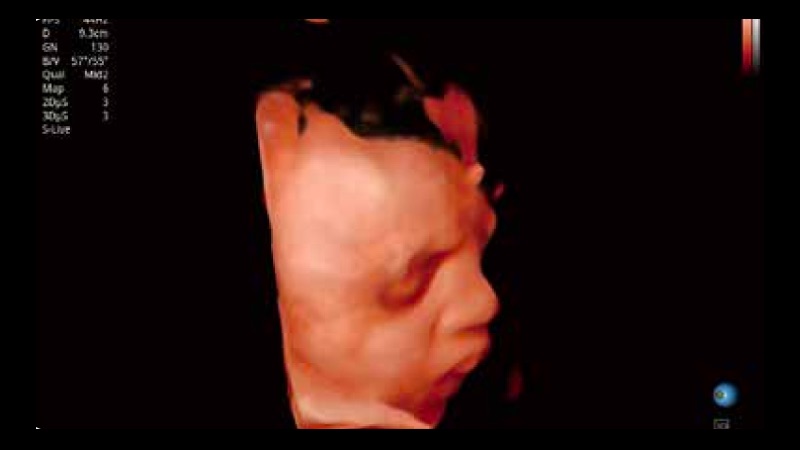

S-Fetus 产科扫查助手

S-Fetus基于大数据深度学习算法,能够帮助您在产前筛查过程中智能识别胎儿标准切面、自动测量并录入报告。一个按键,即可智能、精准、高效地获取胎儿生理指标,极大简化您的产科检查操作。

S-Live 高分辨率容积成像

通过仿真成像技术对3D/4D立体数据进行渲染,多种初始光源位置可选,并支持轨迹球360°光源位置自由调节,清晰显示不同方位容积图像细节。

临床图像